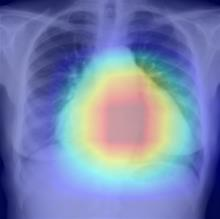

Thoracic disease detection from chest radiographs using deep learning methods has been an active area of research in the last decade. Most previous methods attempt to focus on the diseased organs of the image by identifying spatial regions responsible for significant contributions to the model's prediction. In contrast, expert radiologists first locate the prominent anatomical structures before determining if those regions are anomalous. Therefore, integrating anatomical knowledge within deep learning models could bring substantial improvement in automatic disease classification. This work proposes an anatomy-aware attention-based architecture named Anatomy X-Net, that prioritizes the spatial features guided by the pre-identified anatomy regions. We leverage a semi-supervised learning method using the JSRT dataset containing organ-level annotation to obtain the anatomical segmentation masks (for lungs and heart) for the NIH and CheXpert datasets. The proposed Anatomy X-Net uses the pre-trained DenseNet-121 as the backbone network with two corresponding structured modules, the Anatomy Aware Attention (AAA) and Probabilistic Weighted Average Pooling (PWAP), in a cohesive framework for anatomical attention learning. Our proposed method sets new state-of-the-art performance on the official NIH test set with an AUC score of 0.8439, proving the efficacy of utilizing the anatomy segmentation knowledge to improve the thoracic disease classification. Furthermore, the Anatomy X-Net yields an averaged AUC of 0.9020 on the Stanford CheXpert dataset, improving on existing methods that demonstrate the generalizability of the proposed framework.